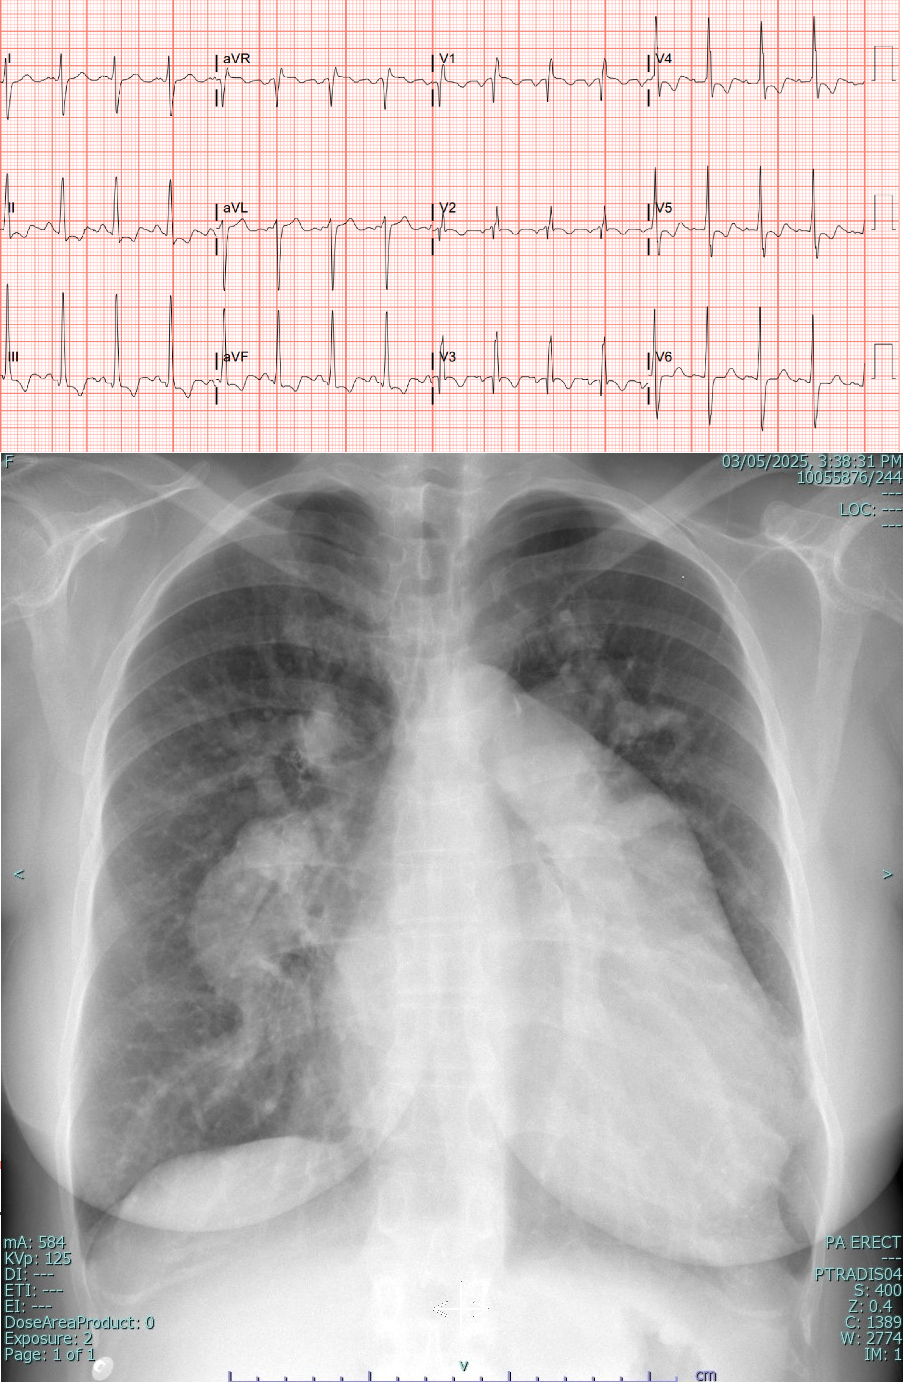

A 55-year-old female with a history of bronchial asthma, dyslipidemia, and an atrial septal defect (ASD) diagnosed in 2005, managed by the Adult Congenital Heart Disease team. She underwent right heart catheterization twice, with the latest Qp:Qs ratio of 0.98 (2015). She has a history of pulmonary artery thrombosis, treated with oral anticoagulants. A recent CTPA showed resolved thrombus and left mainstem stenosis, leading to a planned coronary angiogram.

Relevant Test Results Prior to Catheterization

EF 56% (Simpsons),

Secundum ASD with bidirectional shunt

Dilated RA and RV

CT scan (CTPA and CT coronary) : Resolved pulmonary artery thrombosis, Normal epicardial coronary arteries. ASD measures 3.2 x 2.9 cm